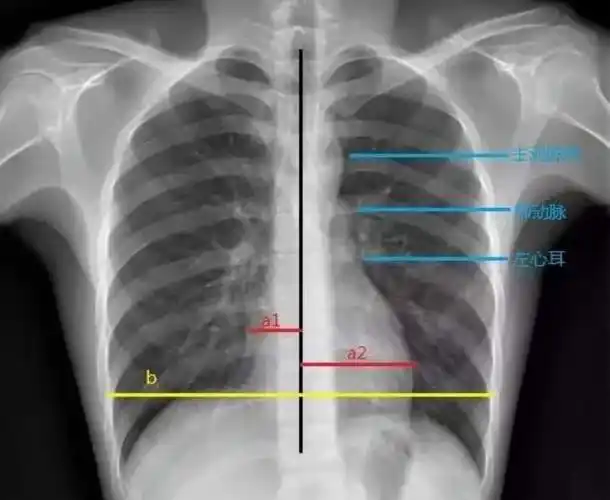

2019年医师实践技能考试x线检查

心包积液(大量):x线:心外形重度增大,各弓弧度消失,呈烧瓶样改变;上